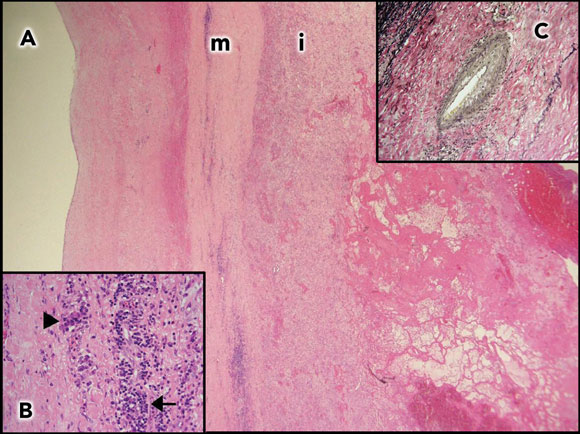

She had an aortic valve replacement, and replacement of the ascending aorta with a synthetic graft. Macroscopically, the aortic wall was extremely thick. Histological sections showed features consistent with syphilitic aortitis (Figure 1). Her recovery was slow, but she is now living independently 15 months after surgery.

1 Aortic wall of Patient 1 ![]() A: Aortic wall (2 x objective) with thickened media (m) and intima (i). |